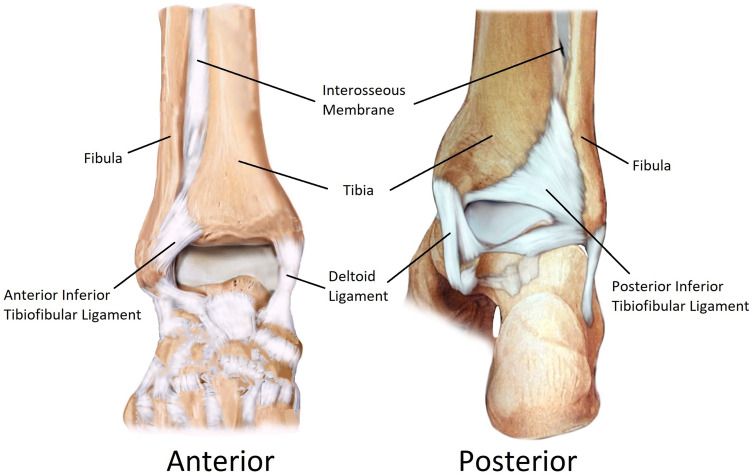

Рис. 5. Анатомия межберцового синдесмоза. Показаны четыре основные связки: передняя нижняя большеберцово-малоберцовая связка (AITFL), задняя нижняя большеберцово-малоберцовая связка (PITFL), межкостная мембрана (interosseous membrane) и поперечная связка (transverse ligament). Адаптировано из Liu et al., 2022, CC BY-NC 3.0.

Четыре связки формируют синдесмотический связочный комплекс: передняя нижняя большеберцово-малоберцовая связка (ПНБМс, AITFL), задняя нижняя большеберцово-малоберцовая связка (ЗНБМС, PITFL), большеберцово-малоберцовая межкостная связка (БММС, TFIL) и поперечная межберцовая связка (TTFL). Эти связки совместно с костными структурами обеспечивают целостность соединения между дистальными отделами большеберцовой и малоберцовой костей, противодействуя осевым, ротационным и трансляционным нагрузкам.